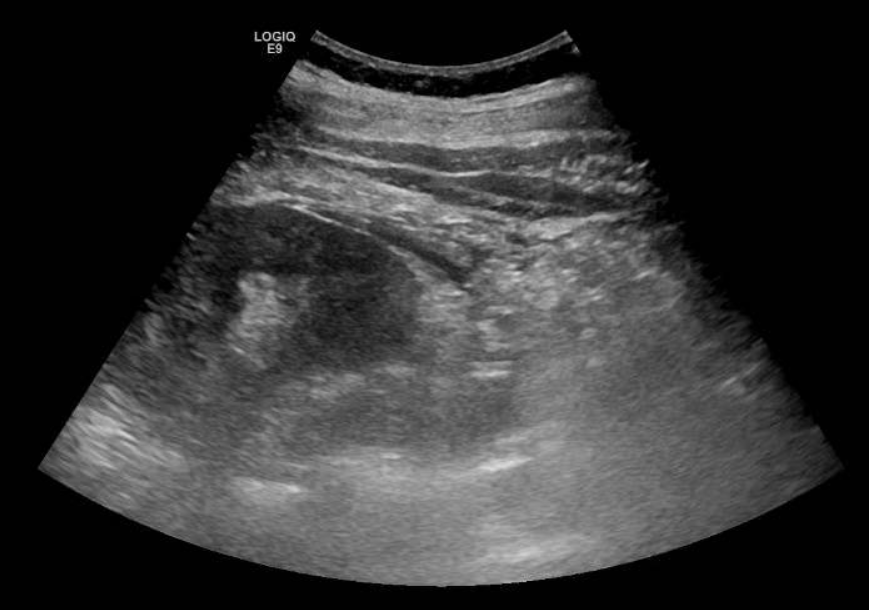

Se solicita ecografía abdominal que muestra líquido en espacio pararrenal posterior derecho bajo, sobre músculo psoasilíaco derecho, y leve ectasia piélica derecha sin identificar causa.

Entre las entidades que afectan al espacio pararrenal nos encontramos linfangioma, entidades fibróticas, hematomas, abscesos, neoplasias… Por tanto, se completa estudio con TAC abdominal con contraste. En el TAC se observa litiasis de 3 mm en meato ureteral derecho con dilatación pielocalicial grado II y leve-moderada cantidad de líquido en espacios retroperitoneales peri y pararrenal derechos, que se relacionan con salida de contraste intravenoso en fase excretora, compatible con rotura de la vía urinaria sin identificarse claro punto de fuga.

Entre las indicaciones de ecografía, se encuentra el dolor abdominal sugestivo de cólico nefrítico en pacientes que no responden a analgesia. La nefrolitiasis es un hallazgo ecográfico muy frecuente en la exploración ecográfica renal y puede acompañarse de dilatación o no de la vía urinaria u otras complicaciones que nos orientarán en el manejo del paciente.